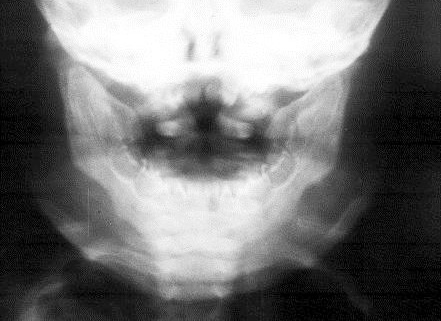

It is another form of FD encountered in children with bilateral swelling of the jaws. The mandible is more commonly affected than the maxilla. Spontaneous regression may occur as the child grows into adults’ stage. Radiological manifestations include diffuse thickening of the jaws (Figure 1).

Figure 1: Cherubism – note the symetrical enlargement of the mandible.